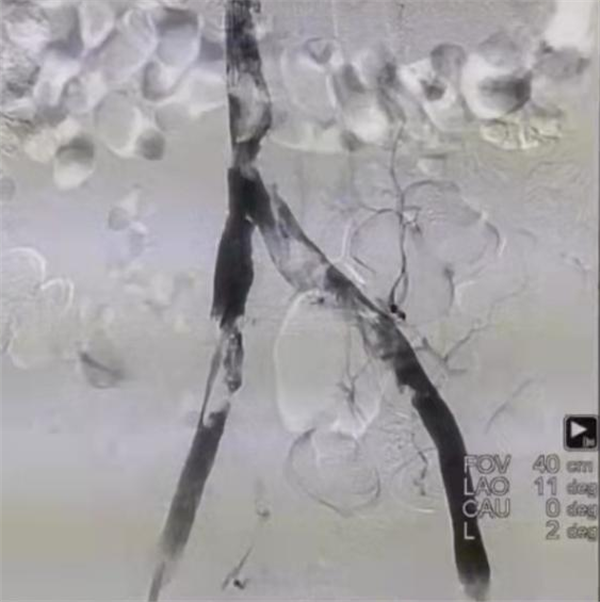

术前造影

患者病情危重,呼吸机辅助呼吸,入住重症监护室,既往患有“格林巴利综合征”,四肢活动障碍,呼吸衰竭,双肺叶肺不张,大量胸腔积液。鉴于该患者病情极危重,而且情况复杂,马建仓教授带领团队,反复讨论,制定方案。由于患者检查结果显示隐血阳性,凝血因子异常,纤维蛋白原低,所以导管接触性溶栓风险极大,所以吸栓就成为患者最为恰当的治疗方案,而吸栓的产品多样,在以往的吸栓手术中常用Anjoget吸栓装置,但是它会导致红细胞破坏,溶血的可能。而最新的AcoStream吸栓装置简单安全,持续稳定的真空负压输出,简单安全,不损伤血管,且高流量抽吸,满足下肢深静脉大负荷血栓清除需求,术中并发症少,所以最终决定使用最新的AcoStream进行下腔静脉吸栓。马建仓教授带领团队凭借扎实的专业基础,以及丰富的治疗经验,为患者成功实施我省首例局麻下AcoStream下腔静脉吸栓术。

术中吸栓过程

该方案从计划到实施,一切都在既定范围内顺利开展,为患者争取了更多的治疗时间。术后效果明显,患者术前腿围左腿34cm,右腿33cm,术后3小时左右腿围均为32cm,术后16小时患者腿围左腿30cm,右腿30.5cm,肿胀程度明显缓解。抽吸除大量新鲜血栓,约30ml,再次造影原布满血栓,无血流的血管内血流立刻恢复,治疗效果立竿见影。

术后造影